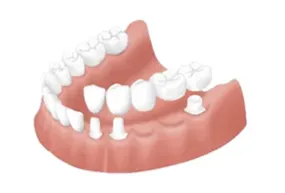

歯の治療には早期発見と早期治療が大切です。歯や神経は生え変わることがないため、今ある自分自身の歯をしっかりと維持し、健康的な状態に保てるように歯科として多角的なサポートをしております。より高精度な治療を行うためにマイクロスコープやエルビウムヤグレーザーなどを導入し、できる限り負担の少ない治療を選択できるように配慮しています。歯の審美性や機能性を向上させる矯正や予防を目的としたホームケアの指導や各種処置、早期発見と早期治療を支える定期検診やメインテナンスなどを湘南台にて実施いたします。

提供している主な治療方法を一覧で掲載しています。お子様からご高齢の方まで、幅広い年代に対応するため、施術方法も多種多様に取り揃えております。